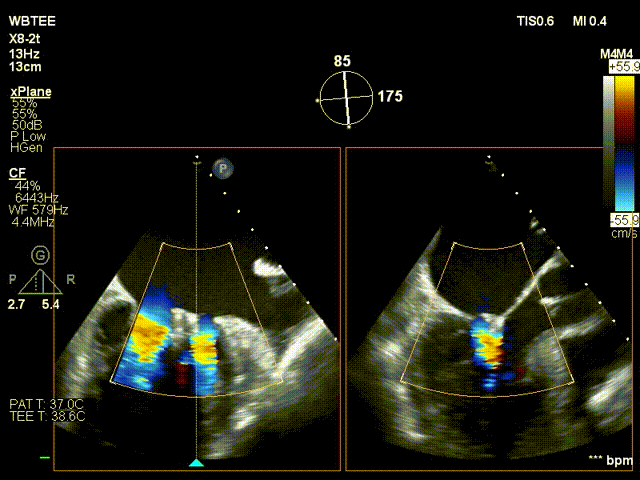

在食道超声王蓓主任的紧密配合下,经食道超声引导后傅国胜教授使用二尖瓣夹准确成功捕获前叶A2和后叶P2反流最严重区域,并予夹合,使二尖瓣在收缩期由大的单孔变成小的双孔,显著减少了二尖瓣反流。

捕捞瓣叶

夹持瓣叶并关紧夹臂

反复测试二尖瓣钳夹的稳定性,超声复查提示二尖瓣夹内侧反流有效改善,外侧仍有部分反流,平均跨瓣压差2mmHg,肺静脉收缩期逆流频谱恢复正向,傅国胜教授团队与超声影像团队充分沟通讨论,计划在二尖瓣夹外侧再置入第二枚二尖瓣夹,遂精准释放第一个二尖瓣夹。